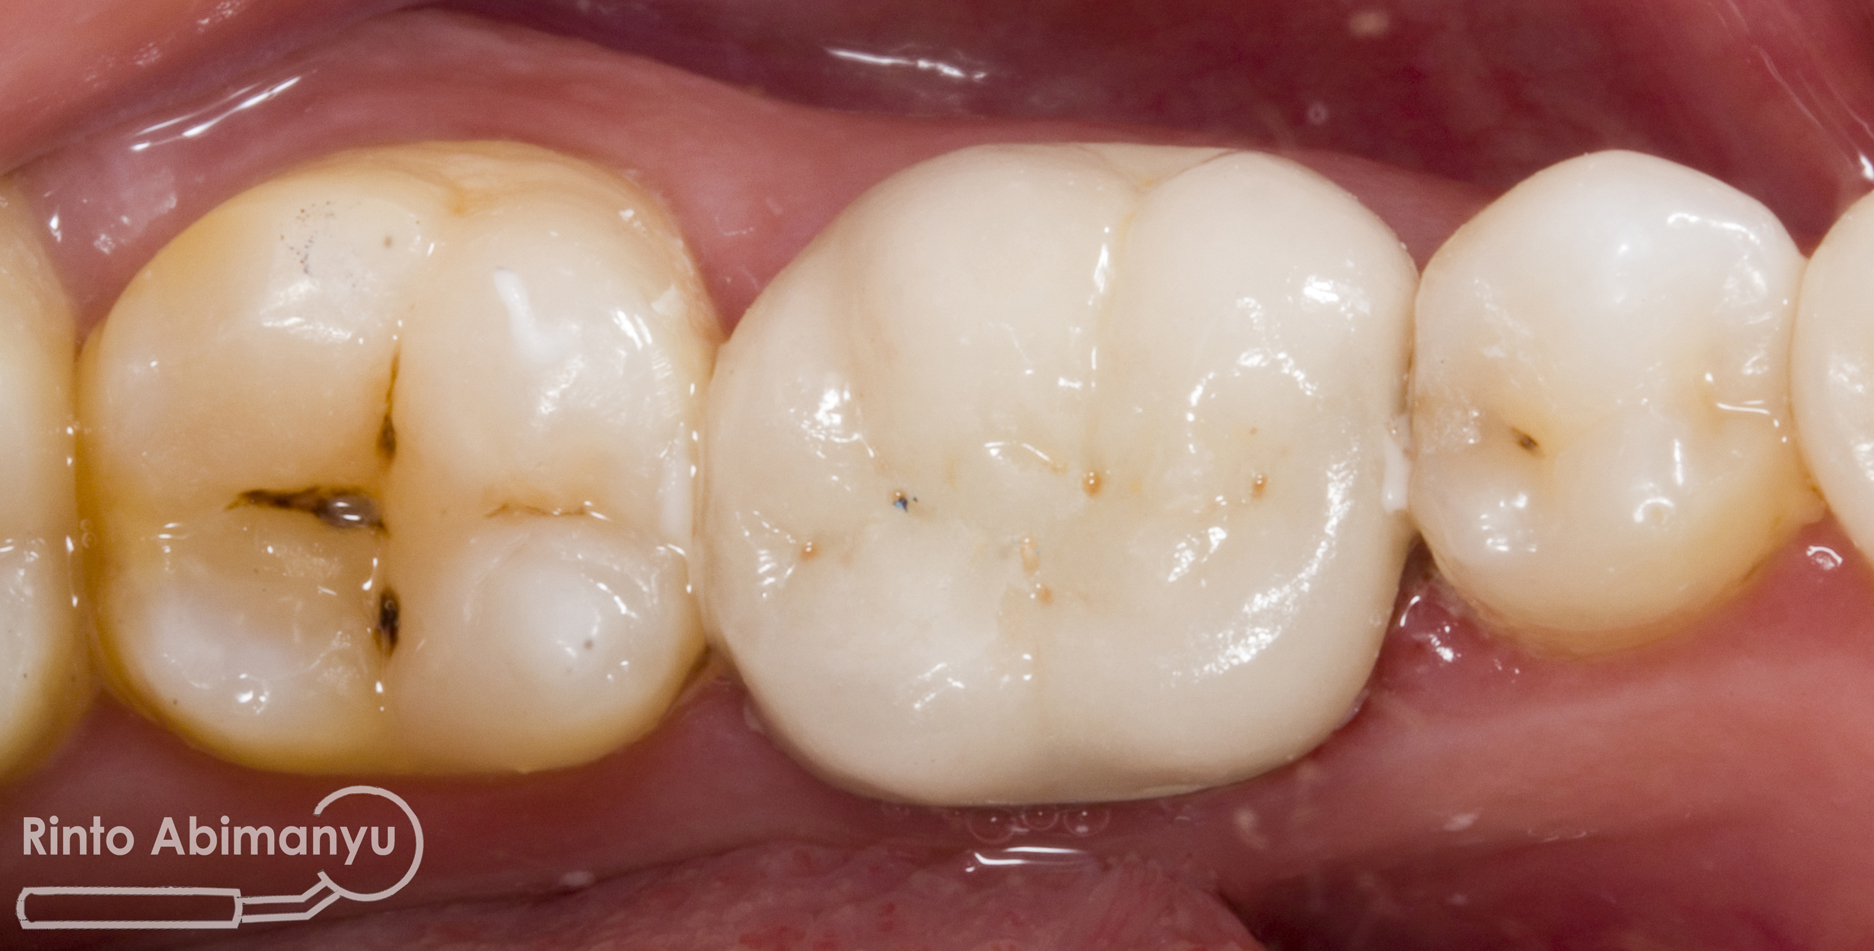

Crown yang saya buat adalah Porcelain Fused to Metal (PFM) dan begini tampilannya sesaat setelah dikirim dari lab…

Dilakukan percobaan crown, dicek retensi dan resistensi, integritas tepi, titik kontak, oklusi dan warna… setelah semua tidak ada kendala maka siap dilakukan penyemenan… Semen yang dipakai adalah GIC Fuji I (GC)..

Alhamdulillah prosesnya berjalan lancar dari mulai perawatan saluran akarnya sampai dengan pembuatan crown… mudah2an awet dan tidak ada masalah… amiiiin….